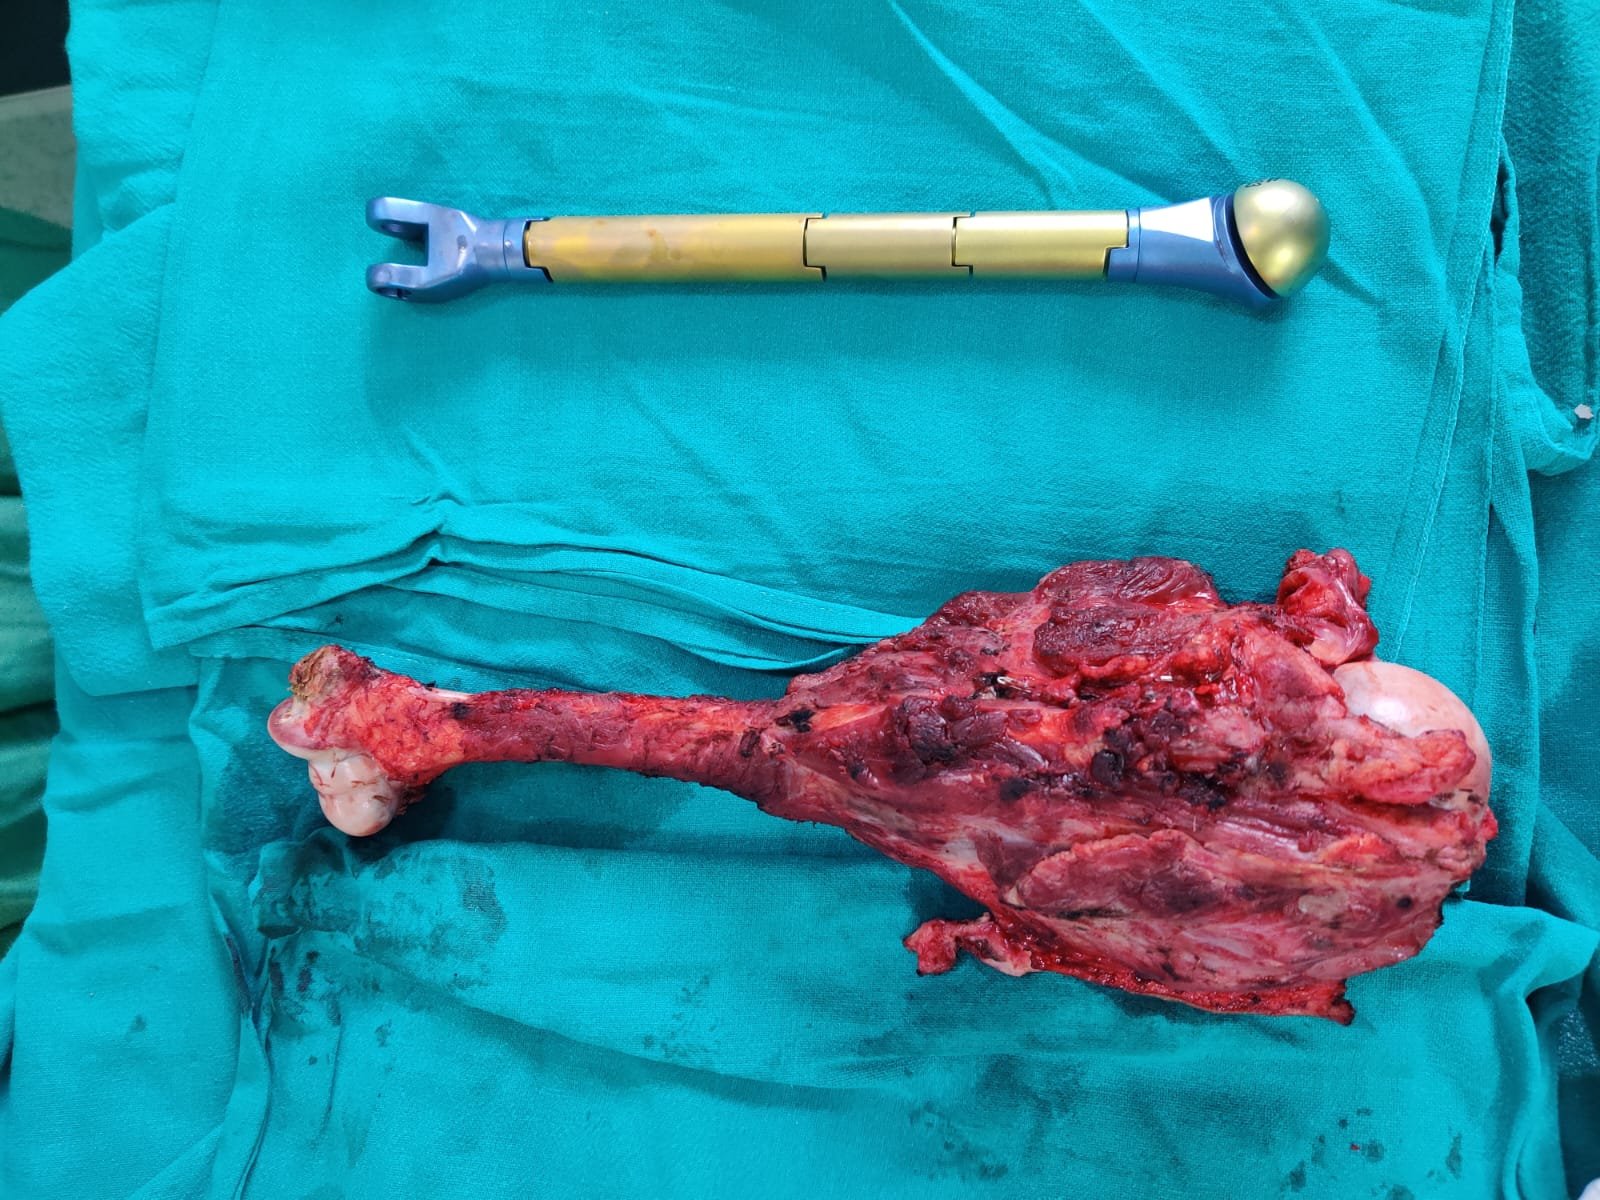

Limb saving surgery with Mega Prosthesis

Young lady with a grade 3 giant cell tumor of proximal humerus with more than 7 year follow up.